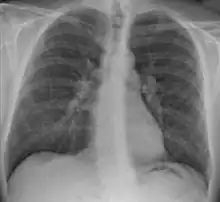

Chest radiograph changes are divided into four stages:[105]

1. bihilar lymphadenopathy

2. bihilar lymphadenopathy and reticulonodular infiltrates

3. bilateral pulmonary infiltrates

4. fibrocystic sarcoidosis typically with upward hilar retraction, cystic and bullous changes

Although people with stage 1 radiographs tend to have the acute or subacute, reversible form of the disease, those with stages 2 and 3 often have the chronic, progressive disease; these patterns do not represent consecutive "stages" of sarcoidosis. Thus, except for epidemiologic purposes, this categorization is mostly of historic interest.[28]